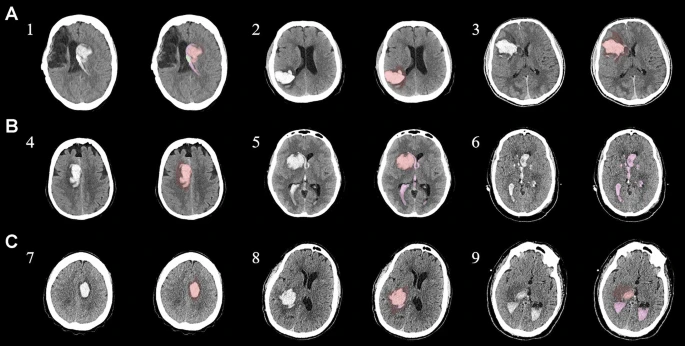

圖1:每個間充質干細胞治療患者按組的原始非對比計算機斷層掃描和分割結果

本研究納入2018年1月1日至2020年10月31日發病168小時內發生急性ICH的患者。間充質干細胞被靜脈注射給9名患者(5名女性,4名男性),平均年齡(范圍)為61(36-84)歲。表1總結了人口統計學和臨床??特征 。出于描述目的,患者按照入組順序獲得編號,并連續分配到三組中的一組,每組三人。根據模型 2 分割,ICH體積范圍為0.1至54.9mL(平均ICH體積為23.5mL)。5例ICH累及局部腦葉,其余則位于基底節或外囊深處。在三名患者中,ICH位于丘腦(圖1),在一名患者中,血腫位于多個腦結構(即尾狀核、殼核和蒼白球)。平均而言,MSC在ICH后3天進行注射。